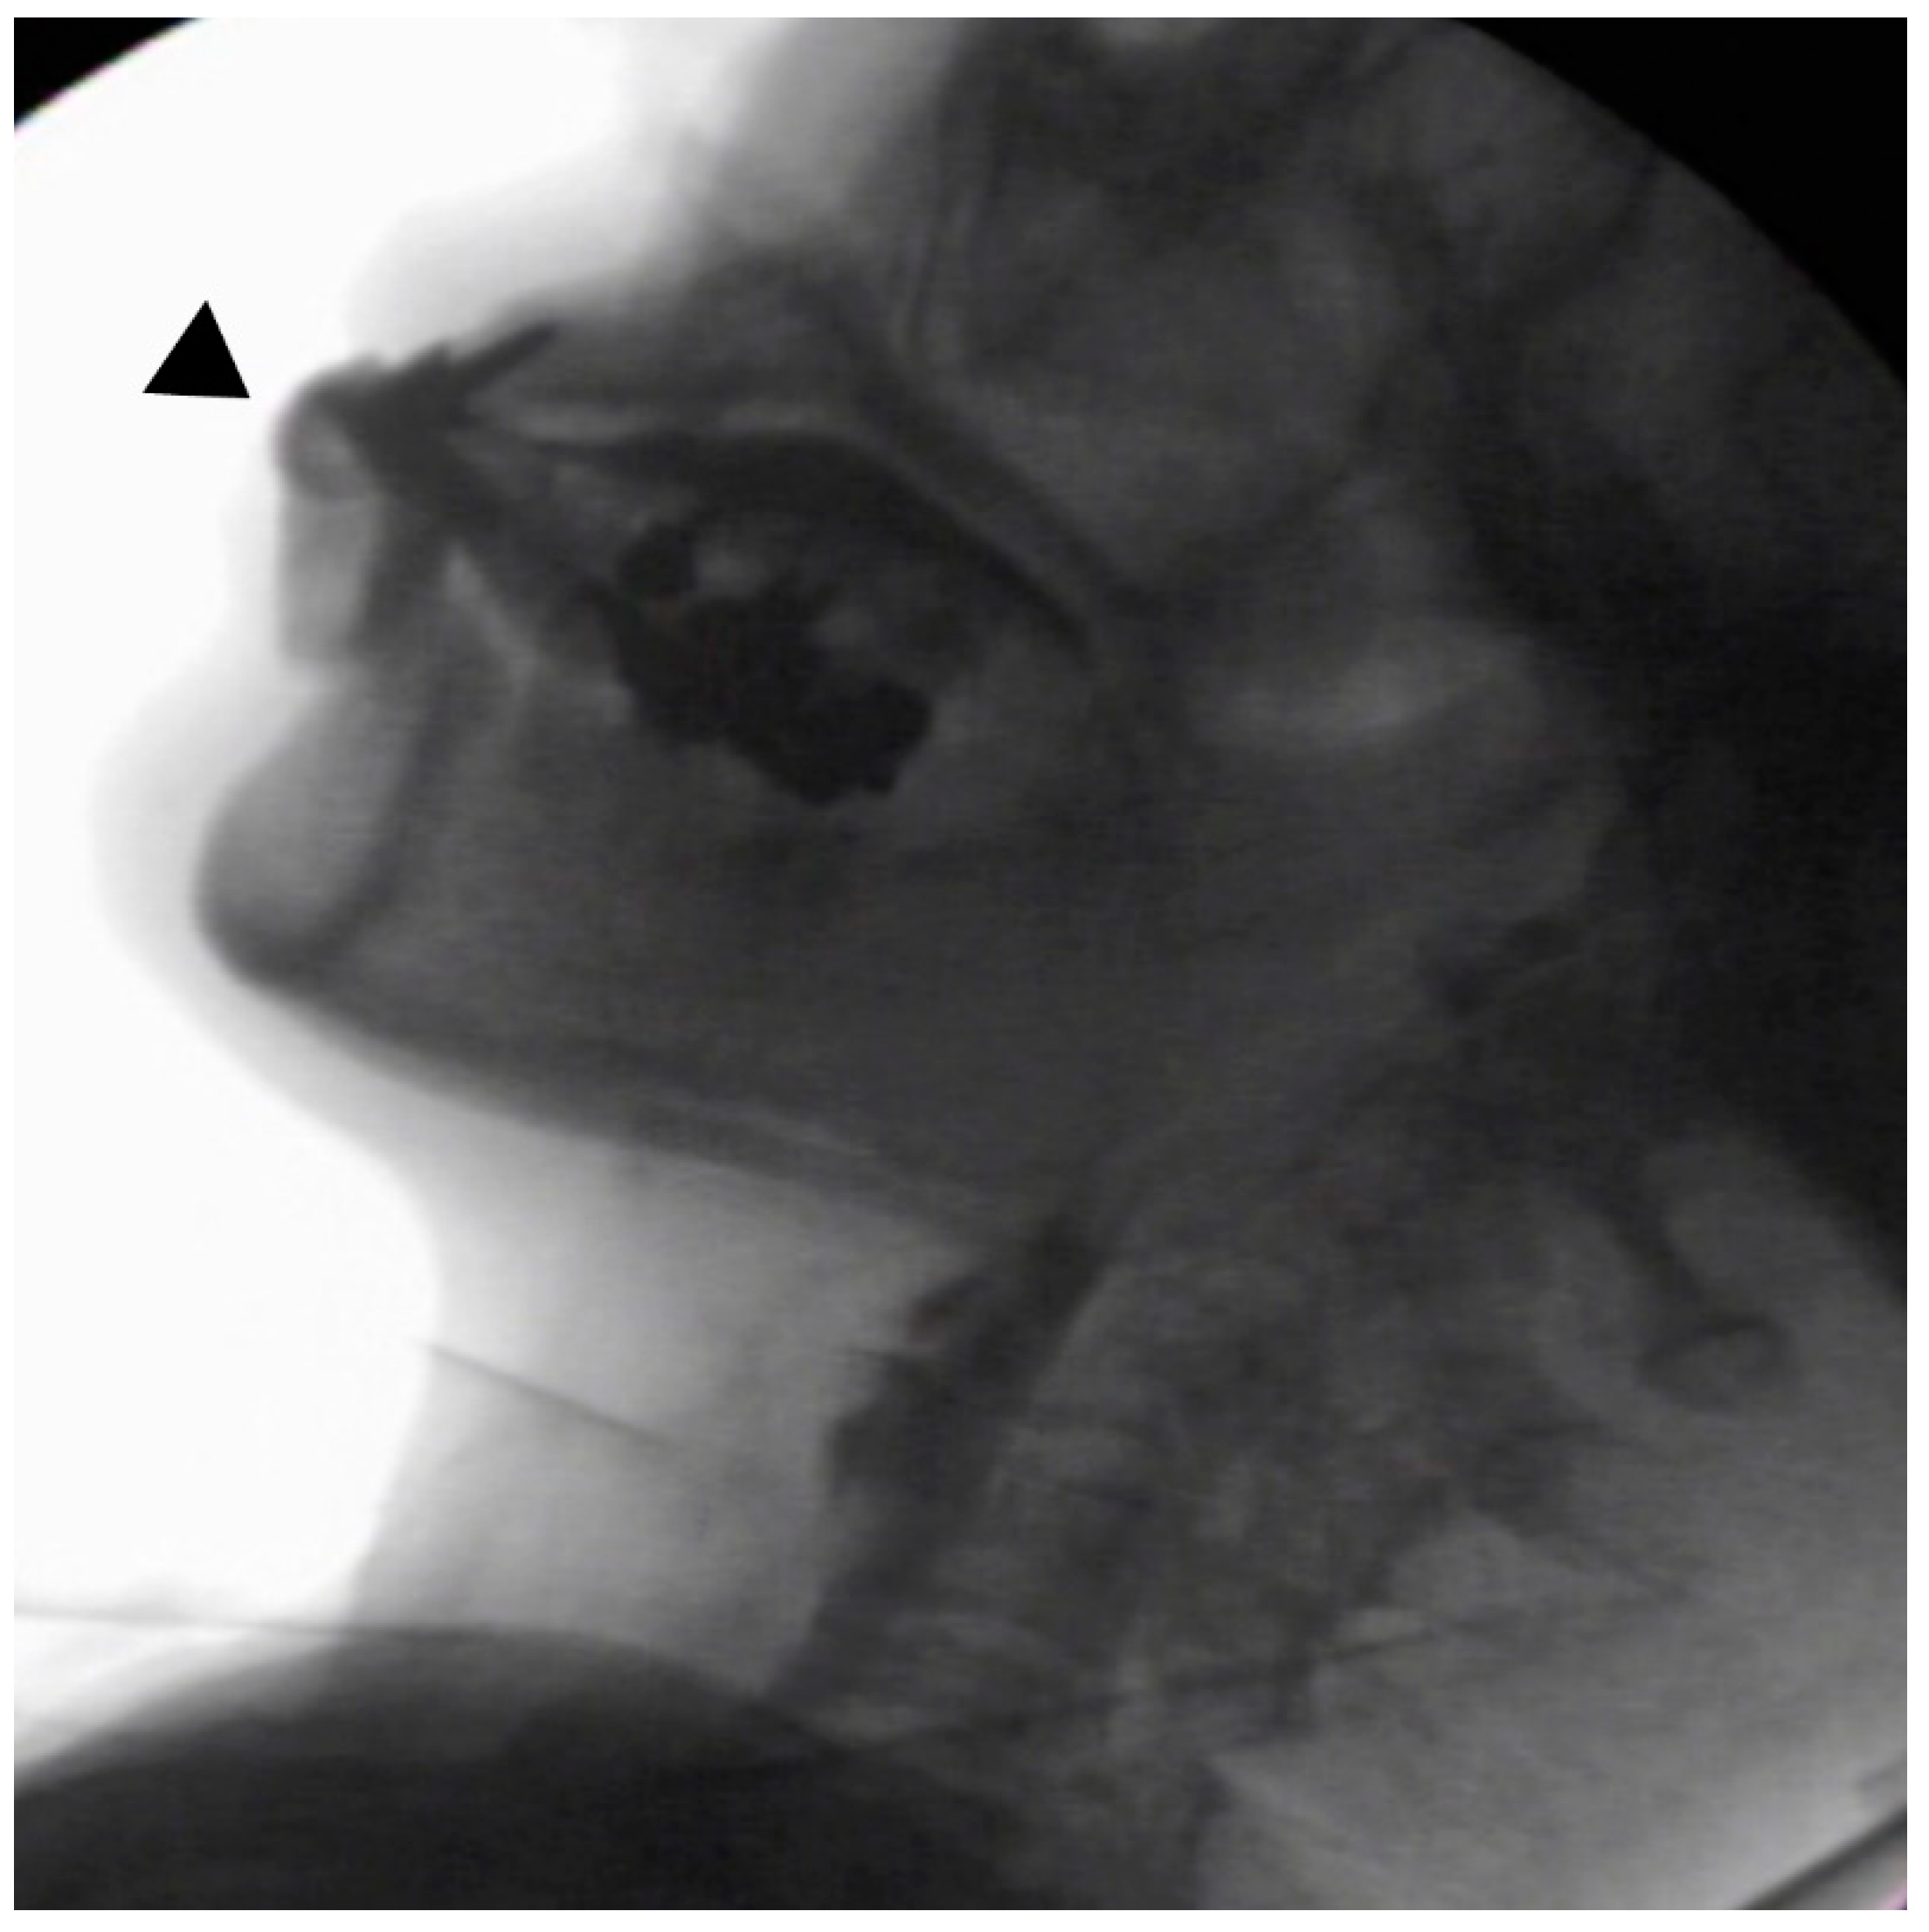

In the seated position, spoon-feeding was infeasible and bolus transport did not occur; furthermore, anterior–posterior tongue movement caused most of the food to dribble out of her mouth. After placing food on top of her tongue using a tube-fitted syringe, most still dribbled out of her mouth (Figure 1a); however, a proportion was transported into the pharynx (Figure 1b). Furthermore, after placing food at the back of her tongue with the patient reclined at 30°, a small amount still dribbled out of her mouth; however, the patient could swallow without aspiration (Figure 2). After increasing the amount placed in her mouth at one time to 7 mL, more food dribbled out of her mouth (Figure 3); additionally, there was a decreased amount transported to the pharynx. When 5 mL of a moderately thick paste was placed in her mouth, none of it dribbled out; however, slight silent aspiration was present (Figure 4). There were no particular issues observed due to peristalsis from the upper esophagus to the stomach.

Figure 3.

The patient was reclined at 30° for the administration of 7 mL of an extremely thick paste. Even when the food was placed in the retromolar area, most of the food dribbled out of her mouth (▲) upon triggering her swallowing reflex.